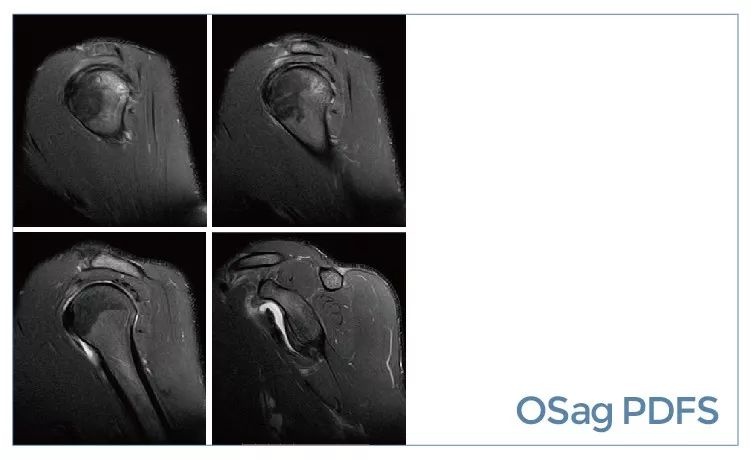

【朗润影像档案】20190927磁共振影像病例结果讨论